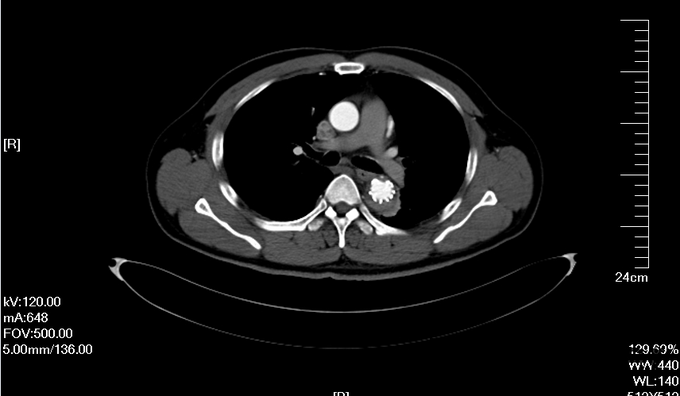

入院查体:体温36.5℃,脉搏90次/分,规则,呼吸18次/分,规则,血压150/80mmHg,胸廓正常,无胸骨叩痛。呼吸运动正常,语颤正常,无胸膜摩擦感,无皮下捻发感,叩诊正常清音,肺下界正常,双肺呼吸音粗,呼吸音对称,无罗音。心音可,心率90次/分,无杂音,腹部无压痛,无反跳痛,肝肋下未及,胆囊无压痛,Murphy征阴性,脾肋下未及,肾区无叩痛,双下肢不肿。入院后完善相关检查(胸腹主动脉CTA:主动脉夹层动脉瘤;两侧胸腔少量积液。)

予以诊断:1.主动脉夹层动脉瘤;2.高血压3级,极高危组。诊断明确后行“左颈总动脉-腋动脉转流手术+胸主动脉覆膜支架腔内隔绝术”。左侧颈部切口,游离出左侧颈总动脉,左侧锁骨下动脉,左侧椎动脉等分支。使用8mmG-tex血管一端与左锁骨下动脉行端侧吻合,G-tex血管另一端与左侧颈总动脉行端侧吻合。经右侧股动脉入路造影见主动脉夹层,破口位于左锁骨下动脉开口医院0.5cm处。左锁骨下动脉近端封闭,桥血管通畅,腋动脉及左侧椎动脉血流良好。置入美敦力胸主动脉覆膜支架(28*157mm),定位后释放。造影见胸主动脉支架释放良好。

主动脉夹层为大血管急诊,B型主动脉夹层相对预后良好。保守治疗效果尚可,近期死亡率相对不高。但对于年轻患者,我们积极治疗。患者B型主动脉夹层,破口位于锁骨下动脉附近。拟行腔内修复术。但患者破口离锁骨下动脉较近,若直接封闭,可影响左上肢活动及椎动脉顺行血流。故根据患者情况行一期复合手术(即“左颈总动脉-腋动脉转流手术+胸主动脉覆膜支架腔内隔绝术”)。术后复查可及左侧锁骨下动脉通畅,血流灌注可。可及假腔内明显血栓化。